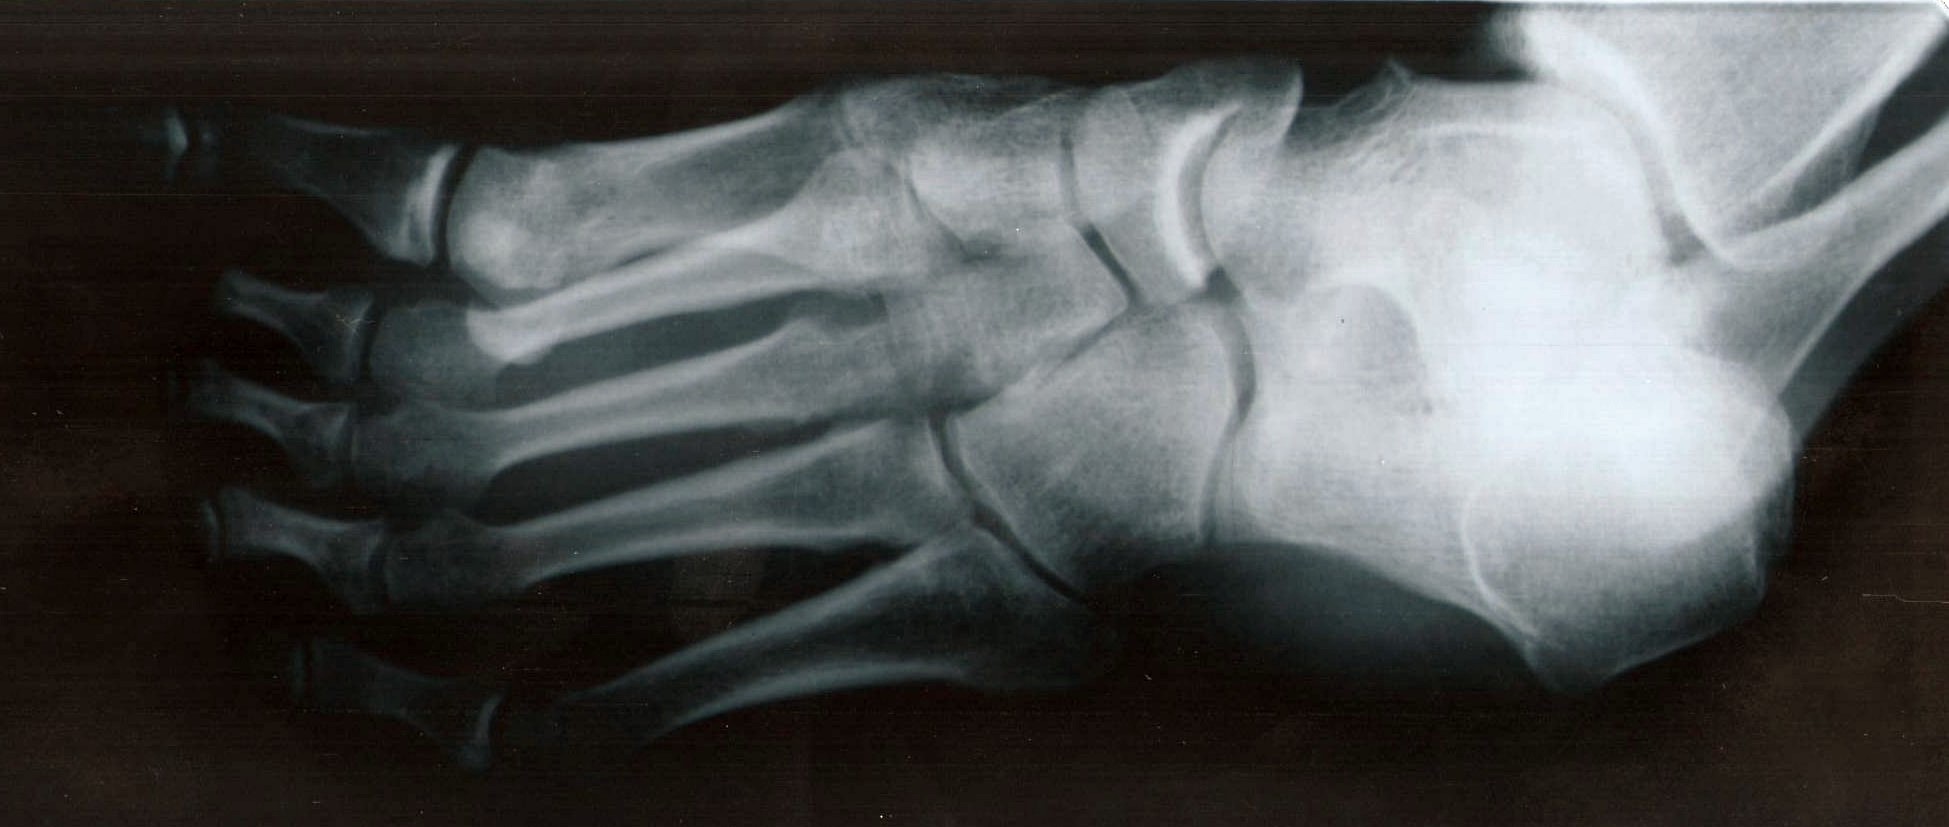

|    Prezados Amigos  Coloco a evolução do trauma no pé direito

que sofri em 20 de março de 2008.

quinta-feira a tarde, trazendo uns tocos cortados para servirem

de bancos no quintal, deixei um cair do porta-malas do carro sobre meu

pé D, batendo em cima (dorso).

Fiz gelo, deixei imóvel, usei Arnica

montana cH12 em alta frequência.